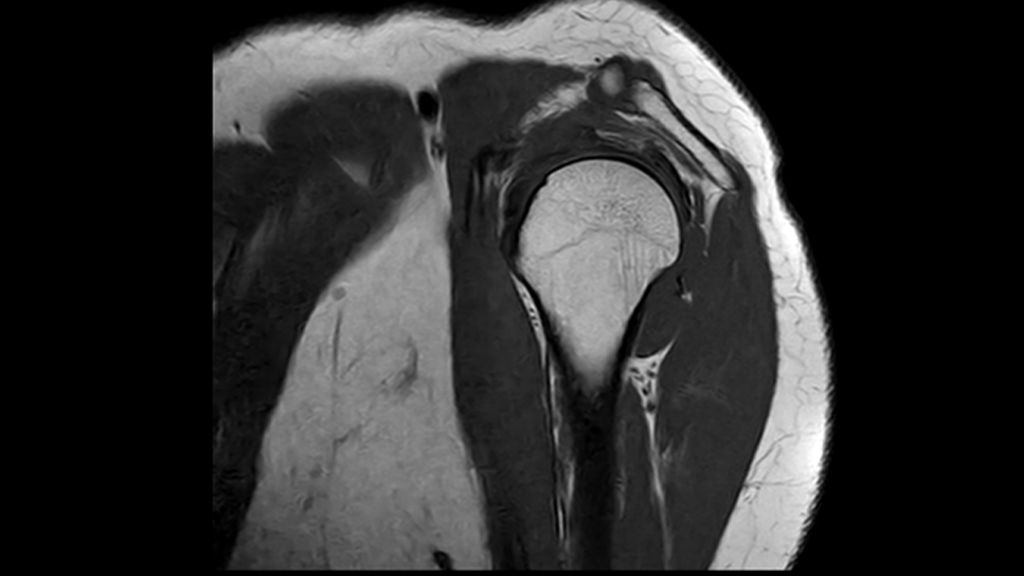

This innovative 1.5T MRI system is powered by Philips exclusive BlueSeal magnet for helium-free operations. And it incorporates a wealth of AI²-driven technologies to simplify and automate the most complex clinical and operational tasks. So you can focus on what matters the most: your patients.

This breakthrough solution is designed to help boost MR productivity, speed up exams, empower clinicians to make informed clinical decisions, and control the costs of MR imaging.